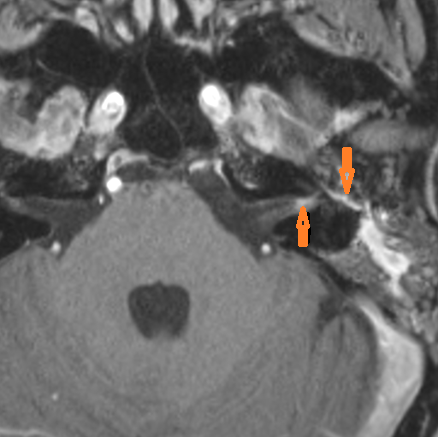

There is a subperiosteal abscess along the outer margin of the mastoid portion of the temporal bone.

The facial canal and nerve are abnormal.

There is evidence of thrombosis, thrombophlebitis or other occlusive or inflammatory process of the sigmoid sinus, transverse sinus, the vein of Labbe’ or jugular bulb

There is evidence of thrombosis, thrombophlebitis or other occlusive or inflammatory process of jugular vein.